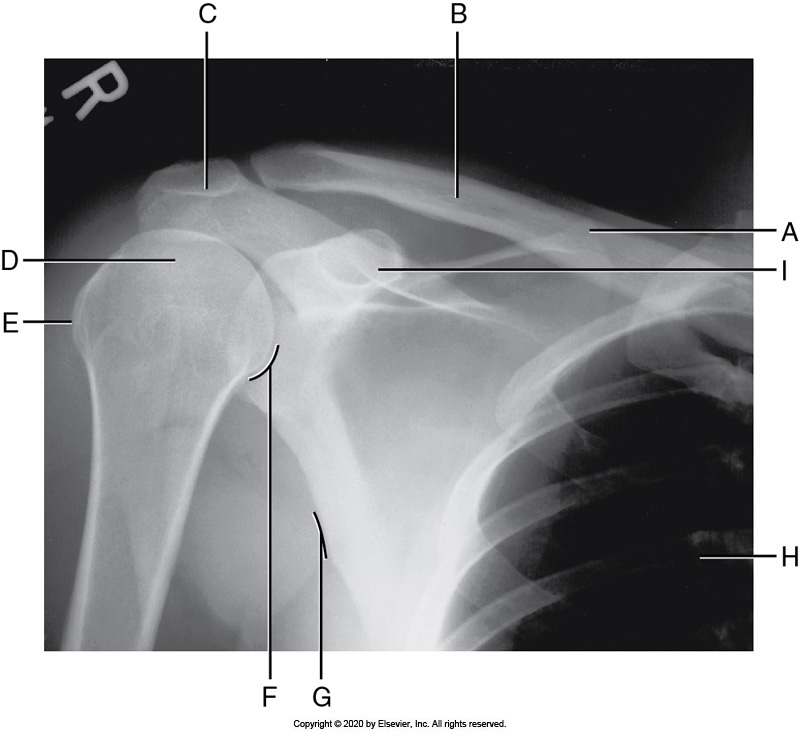

Identify the labeled "I" anatomy in the image below:

Coracoid process

Identify the labeled "E" anatomy in the image below:

Acromion process

Identify the labeled "D" anatomy in the image below:

AC joint